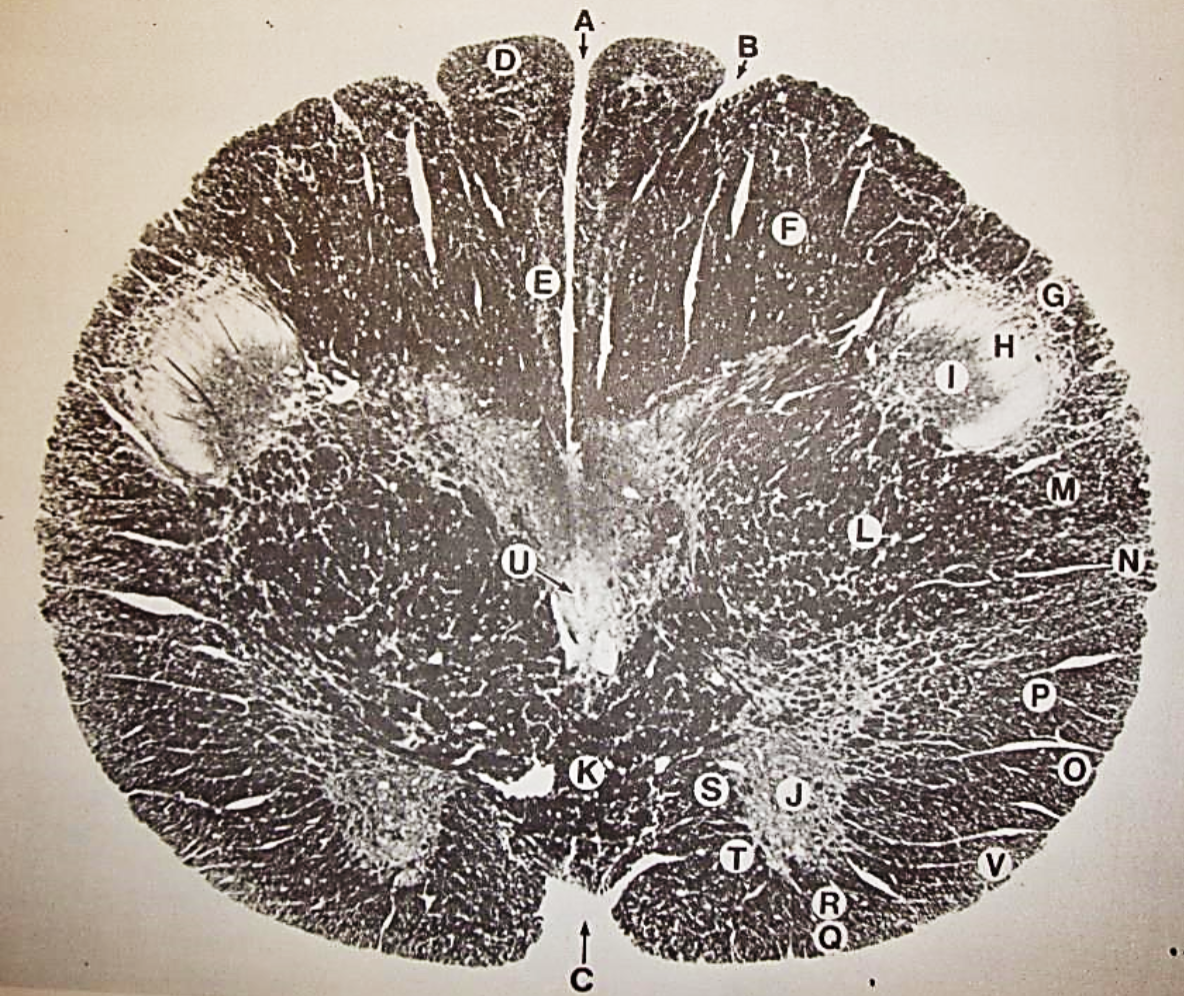

A

fasciculus gracilis

B

gracile nucleus

C

fasciculus cuneatus

D

cuneate nucleus

F

internal arcuate fibers

G

decussation of internal arcuate fibers

H

medial lemniscus

I

hypoglossal nucleus

J

dorsal motor nucleus vagus

K

solitary fasciculus

L

solitary nucleus

M

dorsal longitudinal fasciculus

N

spinal trigeminal tract

O

spinal trigeminal nucleus

P

posterior spinocerebellar tract

Q

anterior spinocerebellar tract

R

spinal lemniscus

S

lateral vestibulospinal tract

T

rubrospinal tract

U

lateral reticular nucleus

V

medial accessary olivary nucleus

W

pyramidal (corticospinal) tract

X

arcuate nucelus

Y

medial longitudinal fasciculus

Z

tectospinal tract

a

fascicles of hypoglossal nerve